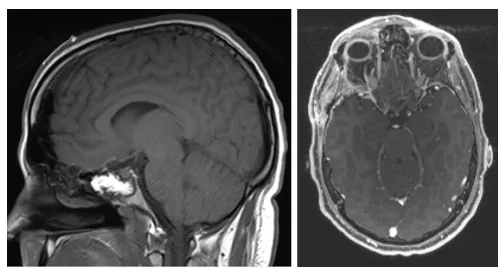

最终,我接受了经额颞入路手术。手术中发现肿瘤质地很软,但已经压迫到了右侧视神经。医生为我切除了肿瘤(图3),视神经管得到减压。术后病理确诊为WHOⅡ级脑膜瘤。

图3.(左)矢状位T1加权及(右)轴位T1加权增强MRI显示病变全切除,未见残留病灶。